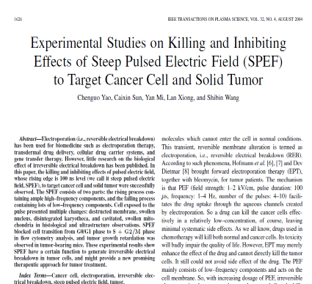

In 2000, Professor Yao Chenguo was the first internationally to propose a novel method for tumor ablation using high-voltage, ultra-short pulsed electric field-induced irreversible electroporation (IRE) and elucidated its underlying bioelectromagnetic mechanisms

In 2004, the first international academic journal paper on killing tumor cells with pulsed electric fields was published in IEEE Transactions on Plasma Science, igniting a research surge in pulsed electric field tumor therapy both domestically and globally